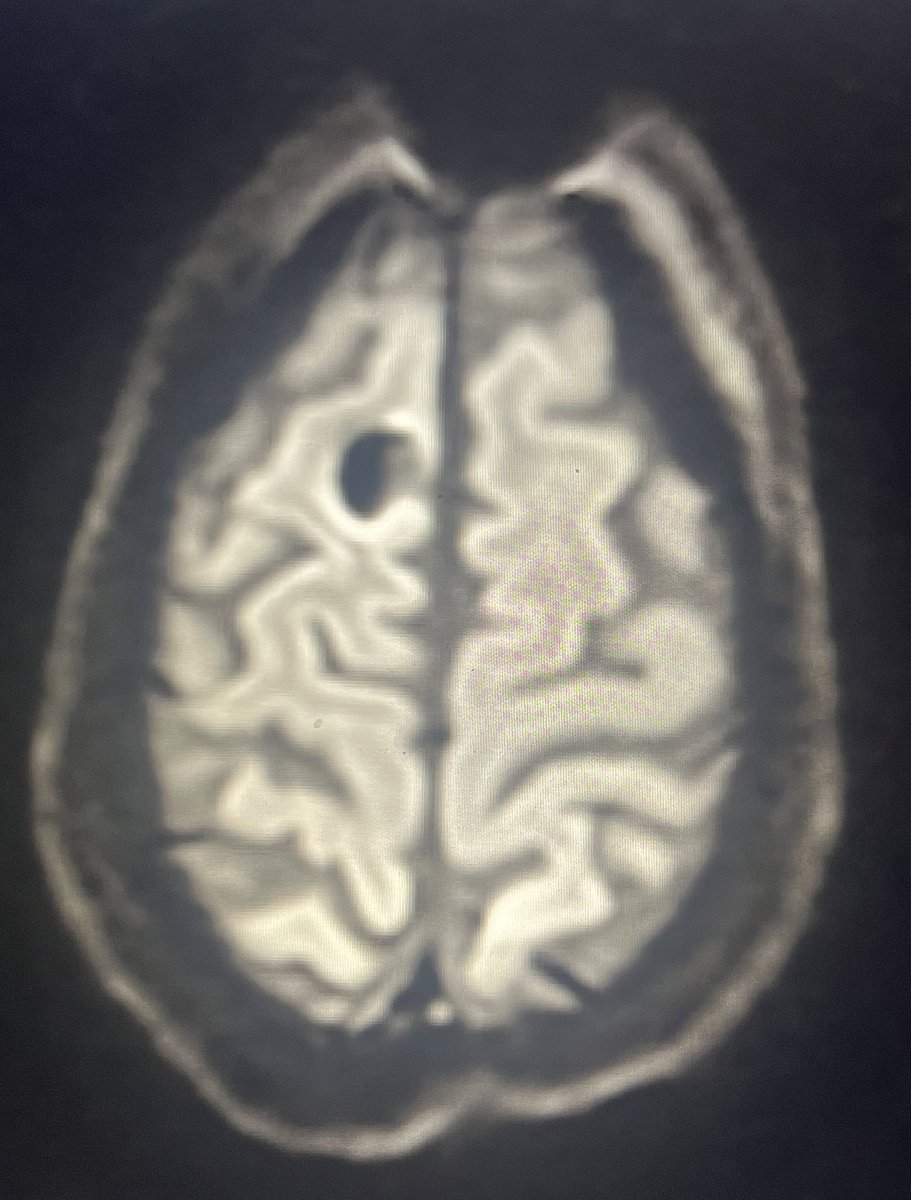

Measles is a highly contagious virus with a primary case reproduction number of 12 to 18.

It is currently spreading rapidly owing to reduced measles vaccination coverage